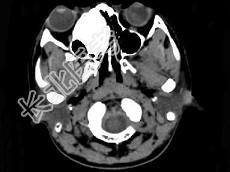

- 多项选择题女,18岁, 眼球轻度突出、眼痛、流泪近半年,CT扫描如图所示, 正确的描述或诊断是 ( )

A、右侧筛窦内见致密骨化影,鼻中隔向左偏

B、致密肿块影向右侧眼眶内突出,右眼内直肌受压

C、筛窦壁及鼻中隔未见骨质破坏

D、副鼻窦(筛窦)内骨瘤

E、副鼻窦(筛窦)内软骨瘤